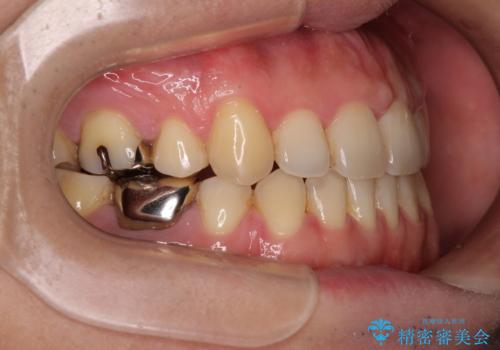

- 抜歯矯正の後戻りを気にして来院された患者様です。

舌の突出癖によるオープンバイトになり、前歯の叢生が後戻りしていました。

舌のトレーニングを行いながら、インビザラインを用いて矯正治療を行うこととしました。

インビザラインの特性を活用して奥歯の咬み合わせを圧下させることで、前歯のオープンバイトを改善さえることができました。